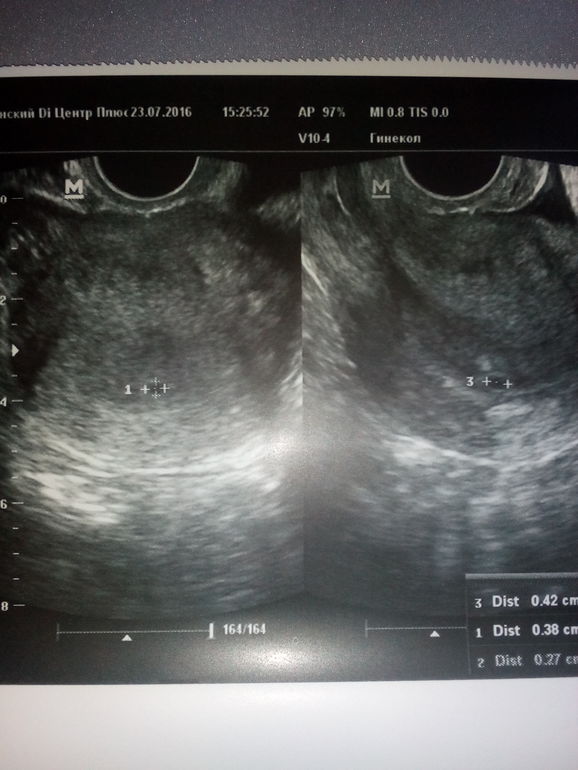

Побывала на узи!!! Все хорошо,нас нашли ,слава Богу там,где и положено!!! Пя 3 ,5мм- срок 3 недельки)))

огорчил один момент- есть киста жёлтого тела((( узистка сказала нужно поддержку- либо дюфастон,либо утрожестан!!! Что скажете ,дорогие ббшки??? Кто сталкивался? Упокойте,,,это же не страшно- страшно?))

у меня вообще 2 кисты желтого тела (как так??). одна 30, другая 38 мм